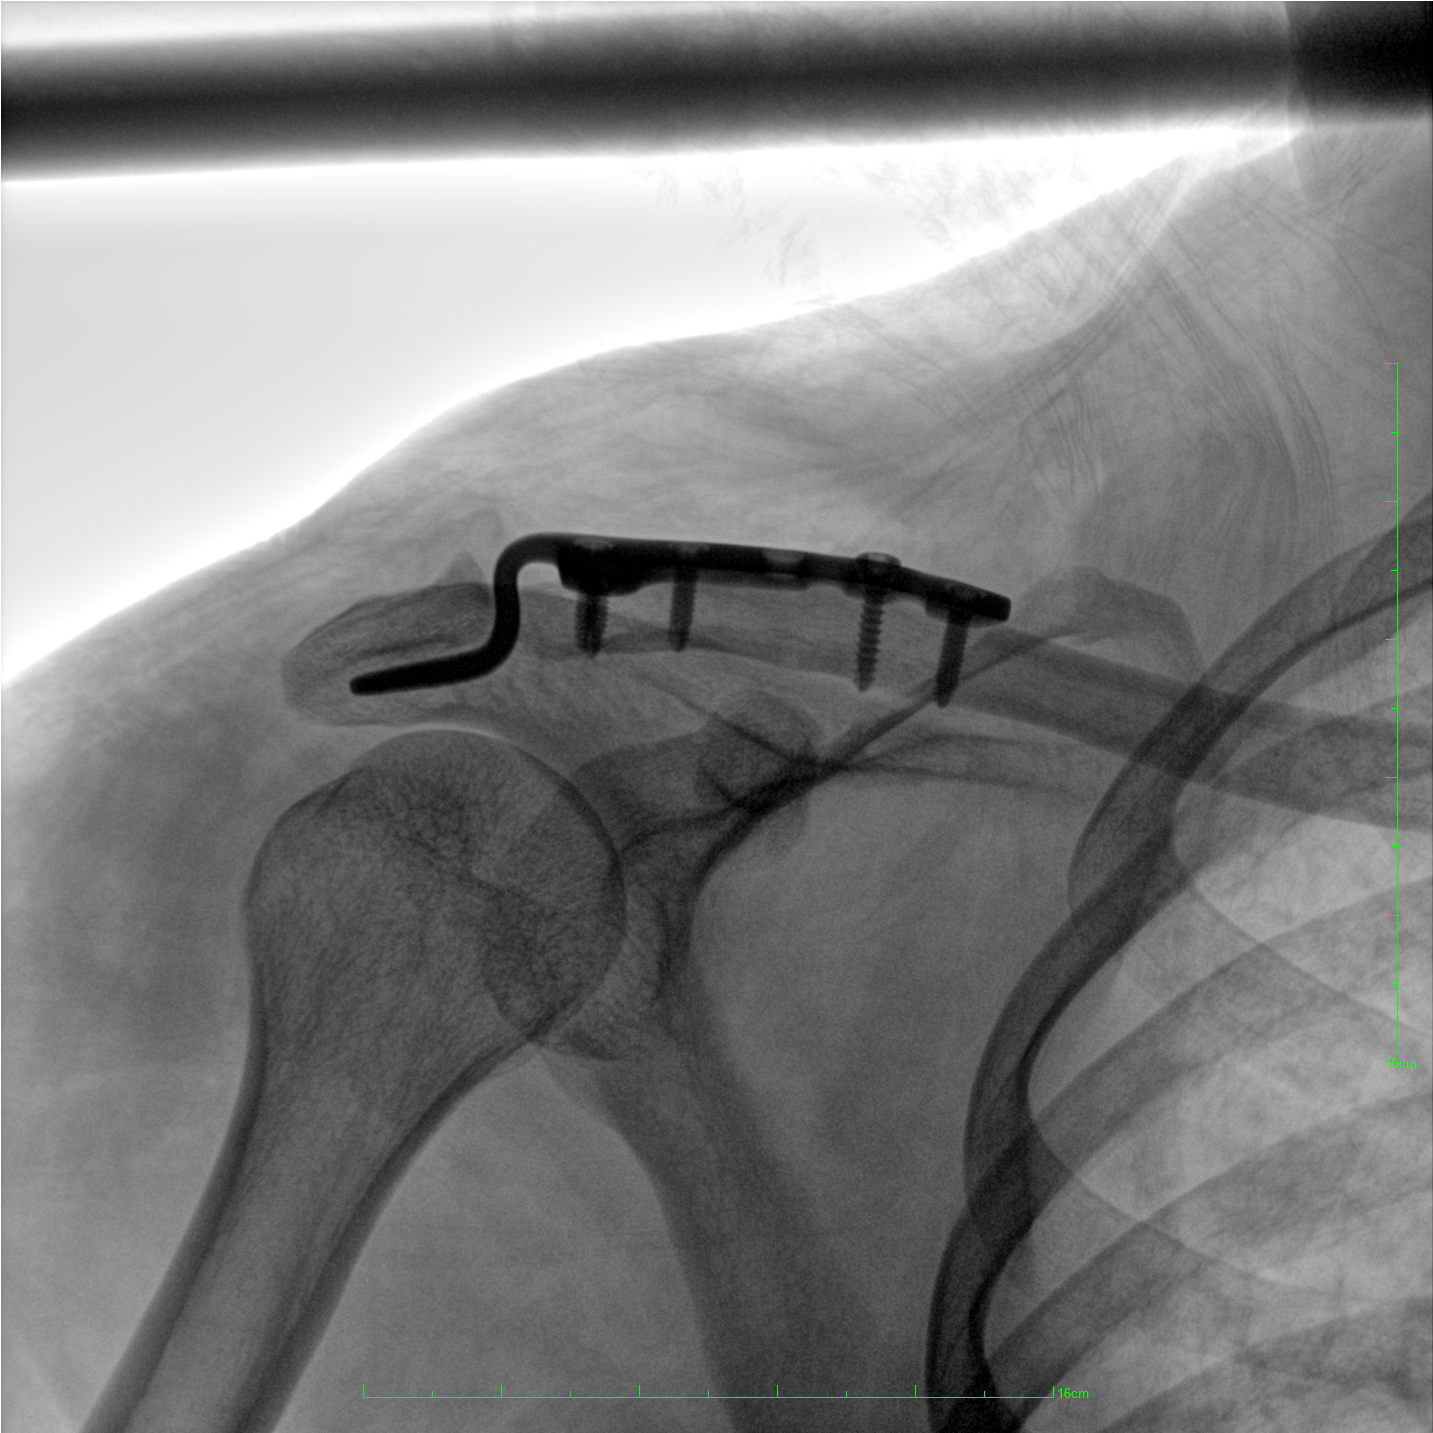

術(shù)中三維成像和橫斷面圖像提供多角度的手術(shù)診斷信息,輔助醫(yī)生進(jìn)行術(shù)中評估判斷,諸如骨折復(fù)位情況和內(nèi)植入螺釘?shù)某叽绾臀恢?,輔助手術(shù)更好地完成。